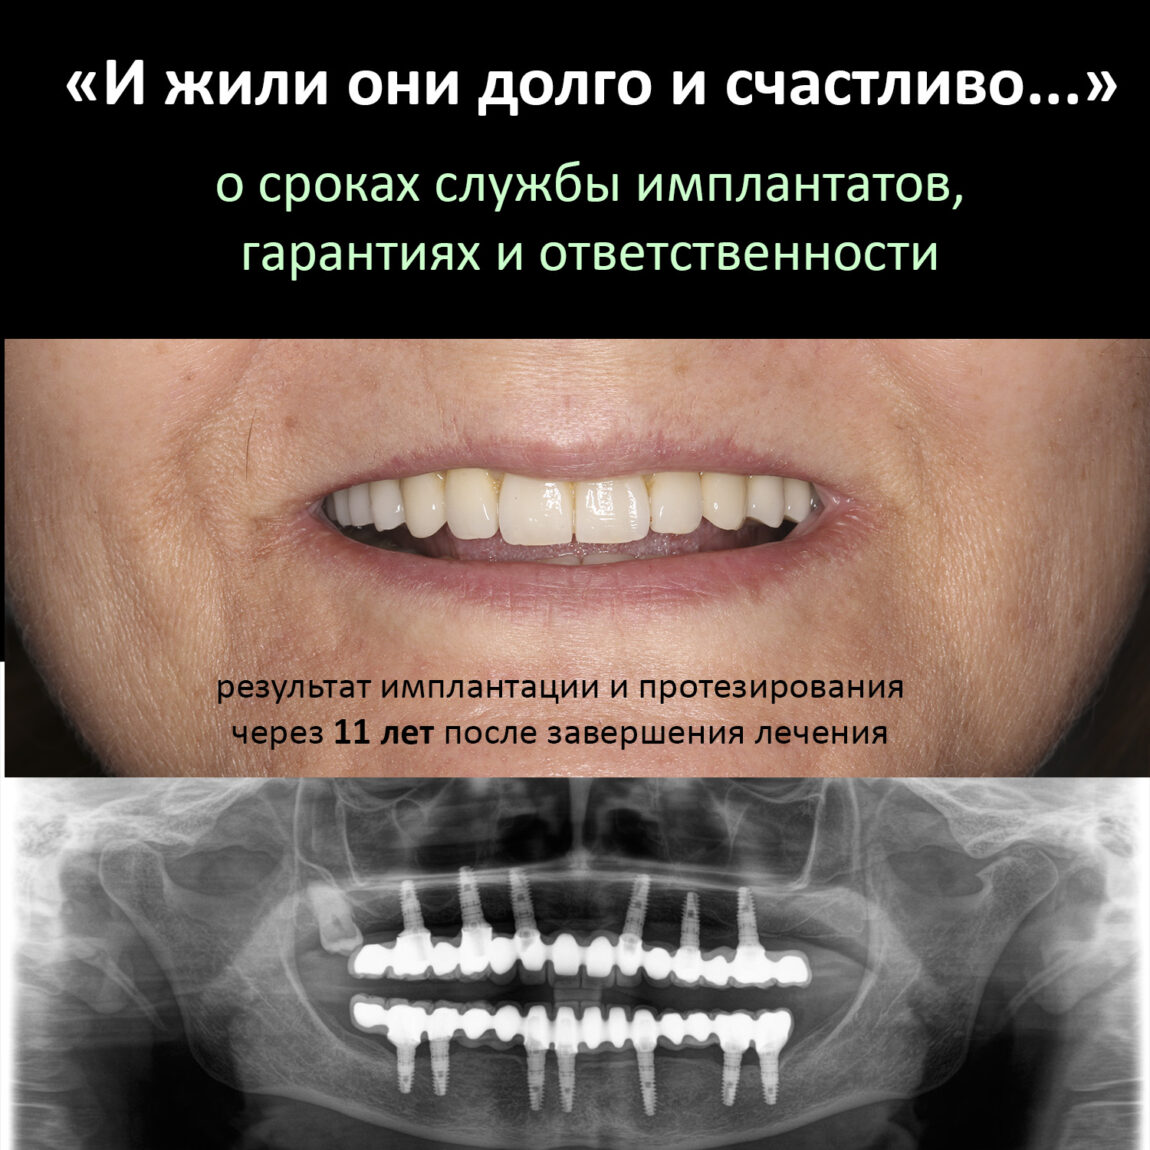

Это пациентка уютной Клиники ИН. Я установил имплантаты Xive одиннадцать лет назад, когда работал в «канАдской стоматологии». Там же её протезировали. По неизвестной науке причине, врач-ортопед выбрал, мягко говоря, неоднозначное протетическое решение — на каждый из тринадцати имплантатов был изготовлен индивидуальный абатмент, а сами зубные протезы были приклеены к ним специальным цементом. Так делать нельзя (объяснение здесь>>). Если бы сейчас кто-то из моих докторов сделал что-то подобное — вмиг погнали бы из клиники ссаными тряпками. С другой стороны, врач-ортопед (он же главный врач «канАдской» на тот момент) в миру известен как жадина и барыга — это вполне может быть причиной выбора цементной фиксации и индивидуальных абатментов там, где этого делать нельзя. К сожалению, иногда бабло побеждает добро.

К счастью Елена (так зовут пациентку) оказалась очень ответственной: каждый год она приходит в нашу уютную Клинику ИН, мы делаем контрольные снимки, проводим профессиональную гигиену полости рта, которую она в течение года поддерживает гигиеной индивидуальной. Она помнит, чего стоило проведенное лечение как по финансам, так и с точки зрения нагрузки на её хрупкий женский организм, потому никогда не пропускает профилактические осмотры.

Собственно, я не зря выбрал в качестве примера столь нетривиальный и даже спорный клинический случай. Он наглядно демонстрирует, что выполнение пациентом рекомендаций по уходу и профилактическим осмотрам обеспечивают длительный срок службы имплантатов даже тогда, когда протетическая конструкция этого, вроде как, не предполагает. Иными словами, «несмотря на все усилия врачей, пациент остался жив» — и продолжает жить полной жизнью, посещая уютную Клинику ИН раз всего раз в год.